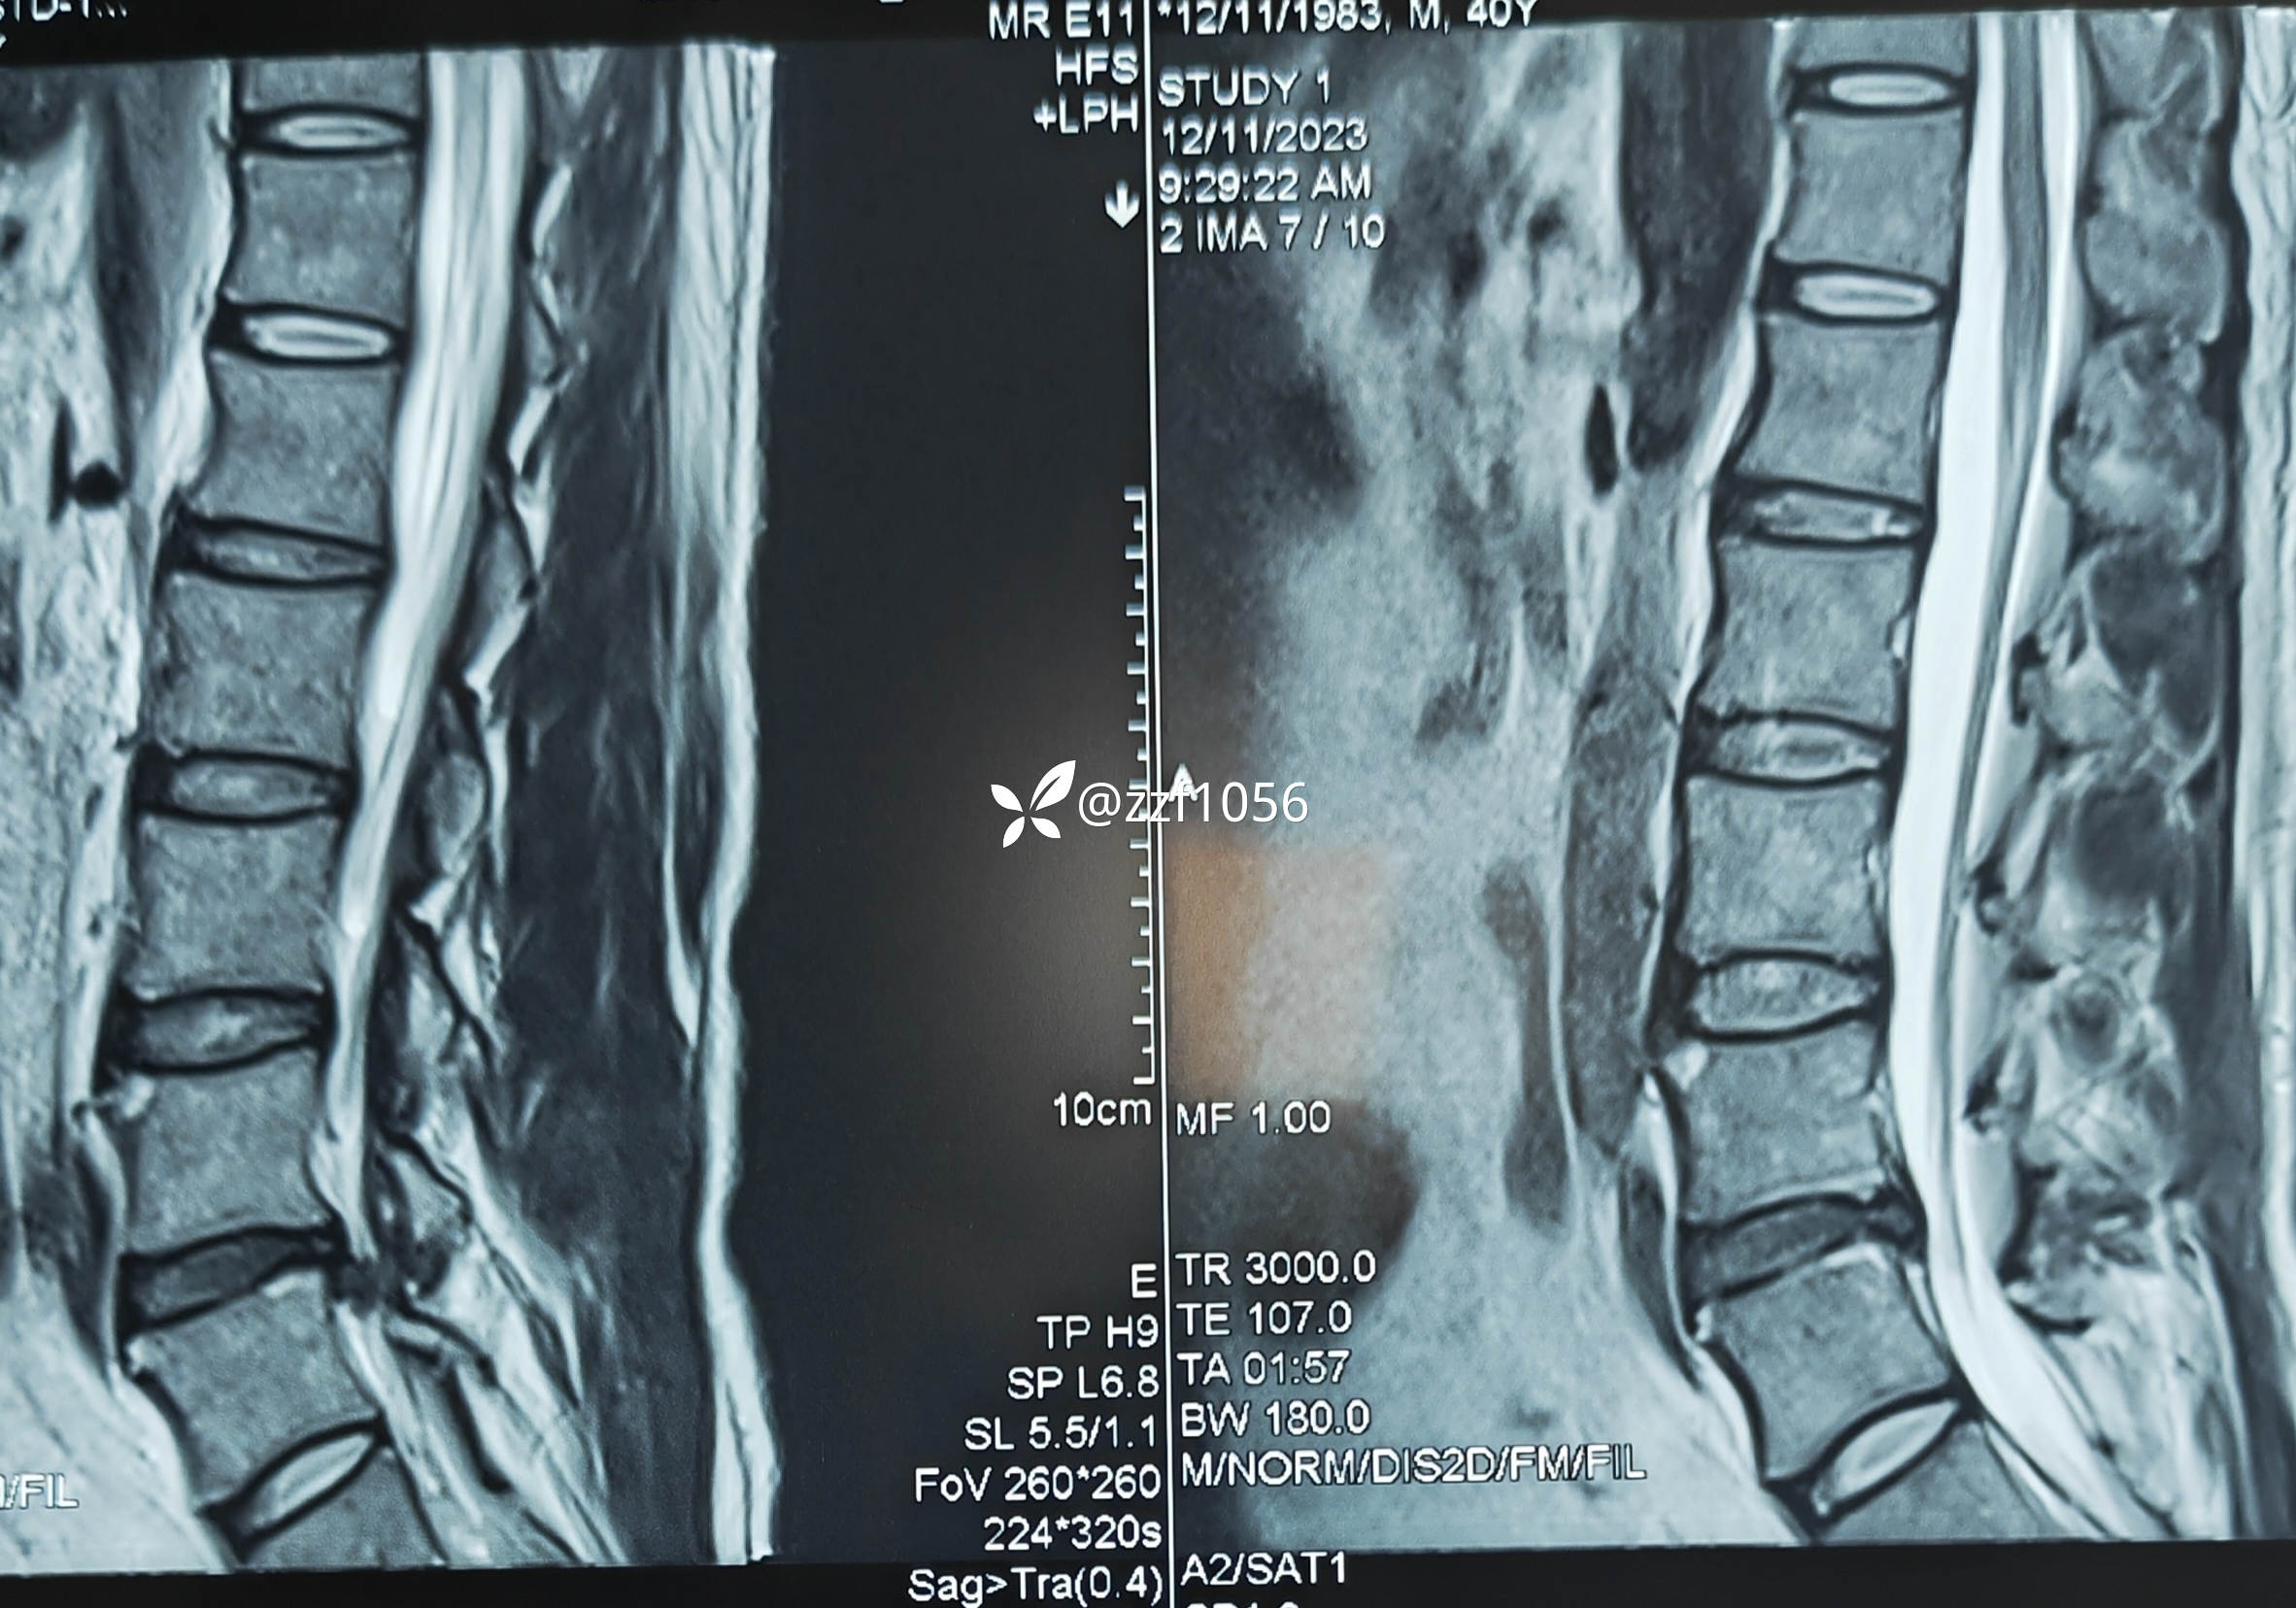

入院诊断:腰椎间盘突出症伴神经根病(L4/5)

侧隐窝处神经根被髓核挤压较重

取出挤压神经根部髓核